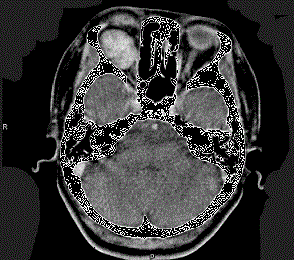

问题 41岁女性,右眼胀痛、眼球外突3月余,体检,发现低头时右侧眼球外突加重,CT检查如图所示,请选择最可能诊断 ( )

选项 A、右侧眶内神经鞘瘤 B、右侧眶内皮样囊肿 C、右侧眶内炎性假瘤 D、眼型格氏病 E、右侧眶内血管瘤

答案 E